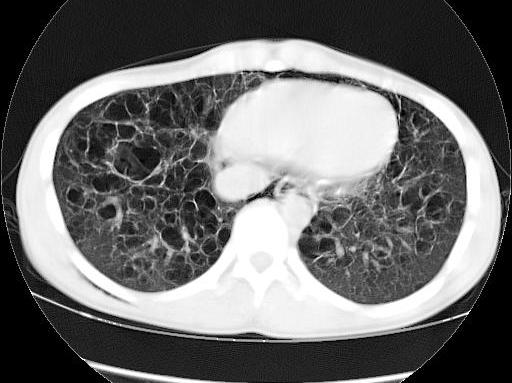

x:双肺中下野多发囊状卷发状影,壁模糊,无液平,双肺纹理强,-------印象:先天支扩并感染.

王某某,男,16岁,既往无经常咳嗽、咳痰、胸闷、发热史,活动与同龄儿童相似,三月前突感胸、颈前痛、无喘憋,查体胸骨上皮下气肿,双肺呼吸音对称。胸部dr及ct示纵隔气肿,双肺囊肿。近两月反复出现胸痛、喘憋,无发热、黄痰及痰血,呼吸音减低,胸部dr示双侧自发性(张力性)气胸,胸腔闭式引流治愈。频繁发作,左侧引流两次,右侧引流三次。

1.诊断考虑先天性肺囊肿(囊性肺),自发性、张力性气胸,鉴别支气管扩张,先天性囊性腺瘤样畸形等

从上述x线片、ct片看,先考虑先天性肺囊肿(囊性肺),伴气胸、纵隔积气、皮下积气;先天性囊性腺瘤样畸形,一般中叶很少累及.

先考虑先天性肺囊肿(囊性肺),伴气胸、纵隔积气、皮下积气,胸水.先天性囊性腺瘤样畸形